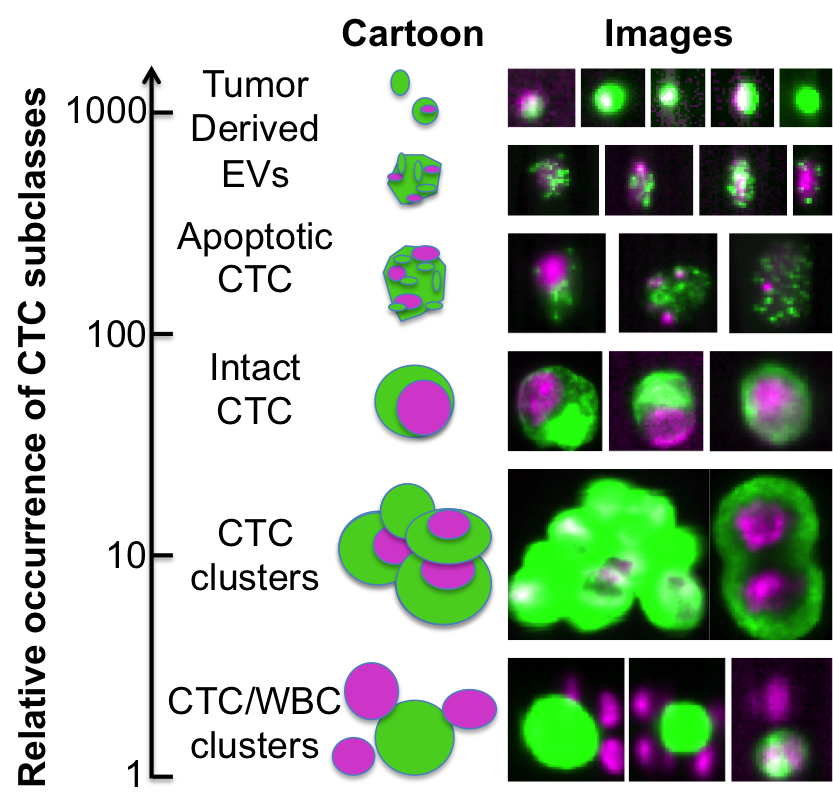

• [ZXSE07] Noha El Zehiry, Steve Xu, Prasanna Sahoo, and Adel Elmaghraby. Graph cut optimization for the Mumford-Shah model. In VIIP ’07 The Seventh IASTED International Conference on Visualization, Imaging and Image Processing, pages 182–187, 2007.